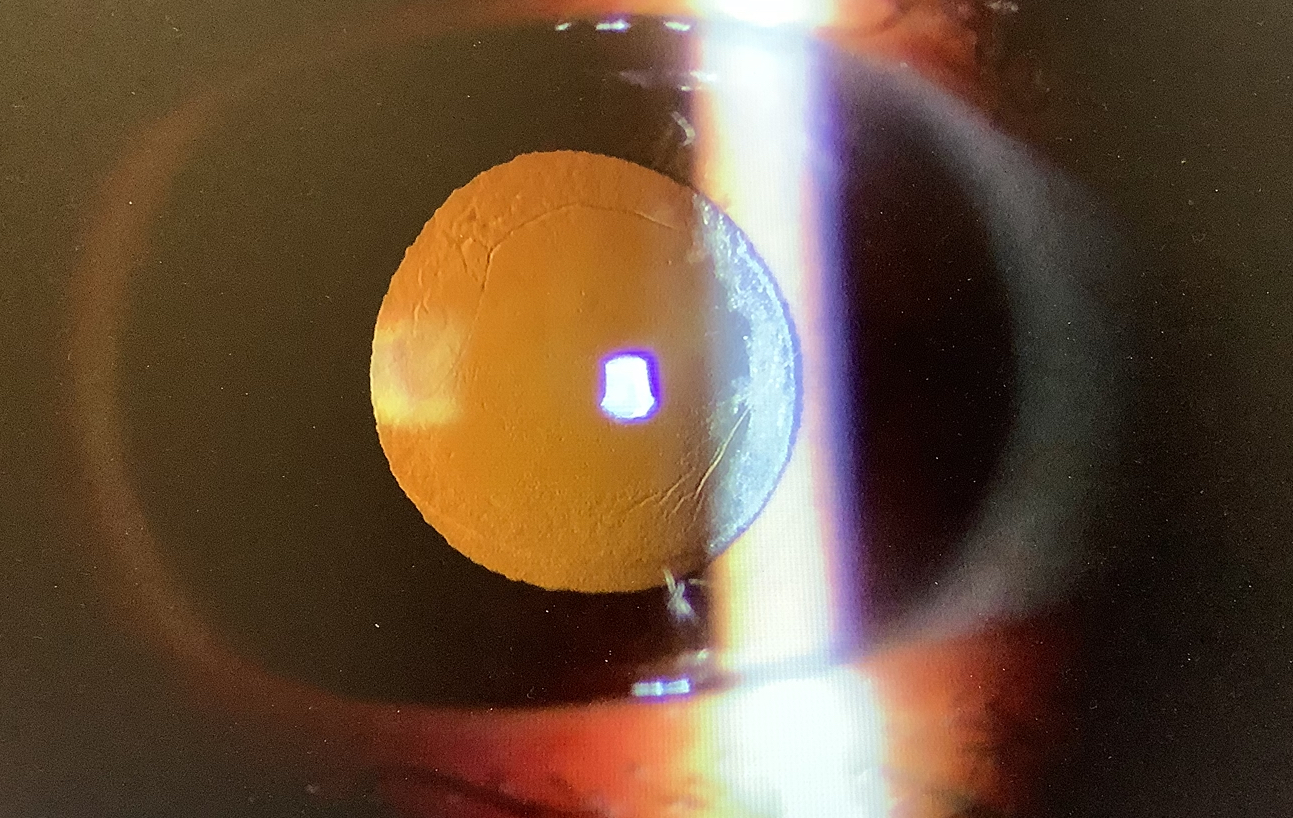

お一人は、50代の女性の方で、他院にて9月に、最初は左眼を単焦点レンズで近方合わせにしたところ、遠方が見えにくいので、右眼は少し遠方めにしてもらい、生活はなんとかできるくらいの見え方は確保できたものの、やっぱり左眼が見えにくく、右眼と合わせたいというご希望でした。レンズの癒着もそこそこあり、入れ換えもできなくはないかとは思いましたが、こだわりがないのであれば、アドオンレンズがよいかと考えていたところ、患者さんご自身もそもそもアドオンレンズを入れるつもりだったということで、その方向で考えていただくこととなりました。

もう一人は50代の男性の方で、この方も他院で9月に両眼同日の白内障手術を受け、右眼は単純な単焦点レンズ、左眼はレンティスコンフォートを遠方合わせで入れたところ、近くが見えにくく、老眼鏡もうまく使えず困ってしまい、当院に相談にいらっしゃったそうです。レンティスは単純な単焦点に比べ、異常光視症も出やすいですし、オントラストも下がるので、片眼は単純な単焦点レンズにしたようですが、この方の場合、レンティスの嫌な見え方はあまり感じず、近くはまだレンティスの入っている左眼の方がいくらか見やすいということなので、まずは右眼をレンティスを-1D程度の軽度の近視に合わせて入れ換えるのがよいのではと提案させていただきました。うまくいけば、右眼で近方を確保でき近方を裸眼で見ることも可能かと思いますし、老眼鏡も使いやすくなるのではと思いました。また、もし、それでうまくいかない場合は、左眼を更に近方に合わせることで、裸眼での近方の視力を確保してあげればよく、その時のバランスも悪くなくできるかと思いました。